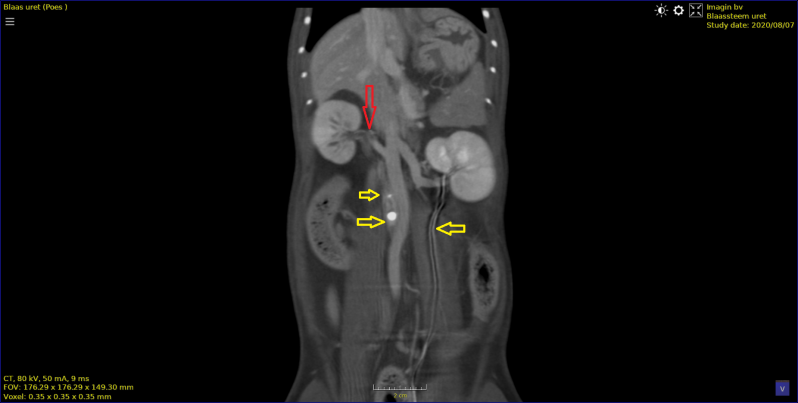

Kat van 6 jaar.

Vermageren en bloed bij urine. Blaassteen, nierstenen en 2 stenen in ureter.

Contrast studie waarbij ,  re nier contrast tot in de blaas loopt en naar de linker nier geen afvoer heeft door obstructie van de ureter door een steen.

u kan een video van deze opname zien op youtube